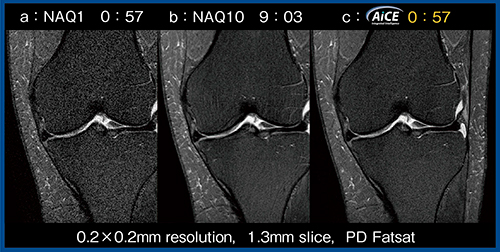

AiCEは,ディープラーニングを用いたノイズ除去再構成技術である。ノイズの多い入力画像をどのように計算すれば高品質な教師画像に近づくかを学習させ,Deep Convolutional Neural Network(DCNN)を構築し,そのDCNNを装置に搭載することで,新たに撮像した低SNR画像のノイズが除去され,SNRの高い画像として出力される。実際に,分解能を上げた1回加算の低SNR画像(図1 a)に対し,10回加算ではSNRは改善するものの撮像時間が大幅に延長する(図1 b)。しかし,1回加算の画像にAiCEを適用することで,同じ撮像時間で10回加算と同等のSNRが得られる(図1 c)。

図1 AiCEによるデノイズの効果